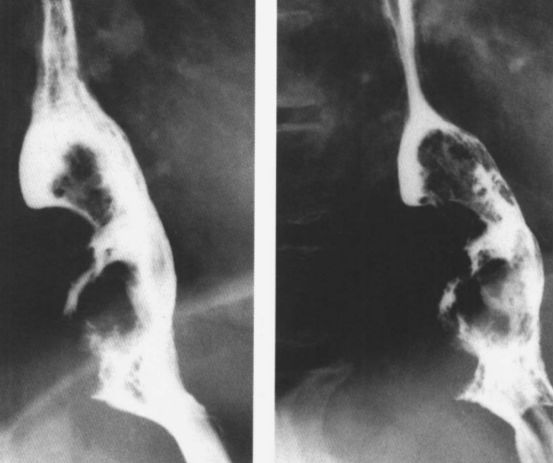

贲门失弛缓:鸟嘴征。

中度贲门失迟缓

重度贲门失迟缓